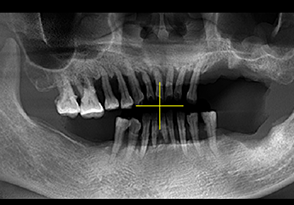

A.将CBCT数据导入软件中

B.绘制下颌神经管

1.CT数据导入

2.成像预览